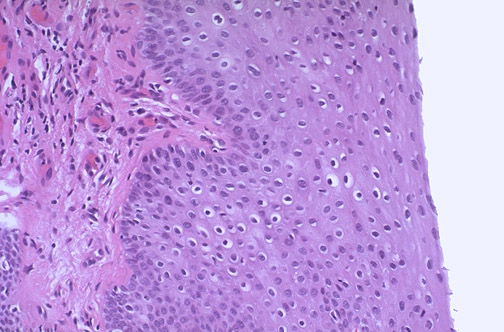

| At medium magnification the condyloma, which is the result of human papillomavirus (HPV) infection (usually subtypes 6 and 11), demonstrates vacuolization. The condyloma itself is not premalignant, but persons with these lesions may have other lesions with other subtypes of HPV that can progress to dysplasia and malignancy. |